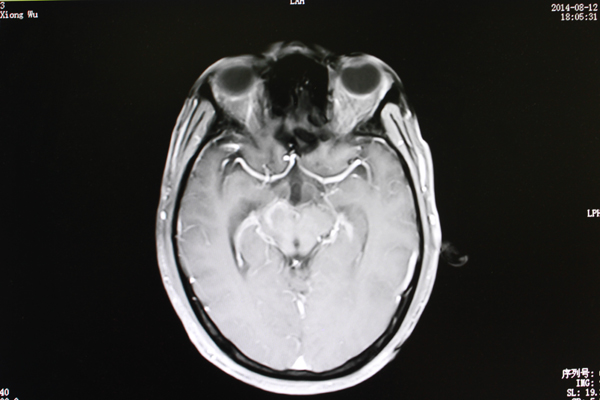

• 脑干长肿瘤不能开刀?射波刀一解难题

脑干长肿瘤不能开刀?射波刀一解难题

41岁的黄先生在平南县从事农贸生意,家中儿女双全,本过着幸福的生活。然而两个月前黄先生莫名出现头晕,左耳耳鸣的情形,以为是小毛病就不太...